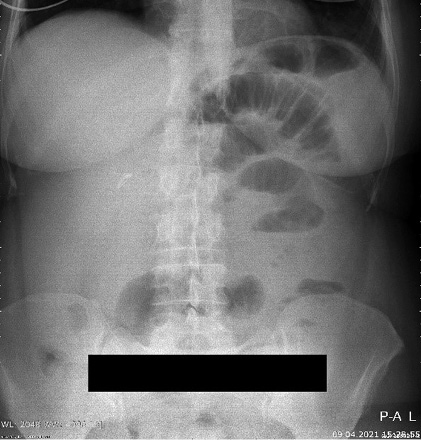

A 46-years-old female patient presented to the emergency department with clinical signs of intestinal obstruction. The patient reported cramp and abdominal pain, and absence of flatus and stool passage one day prior to the exam. She had no previous abdominal surgery nor visible groin herniation on physical examination. The serum analysis showed C-reactive protein value of 5.80 (0.0–5.0 mg/L) and serum Iron level of 5.80 (6.6–28.3 μmol/L). Plain abdominal upright X-ray image confirmed the suspicion for intestinal obstruction (Figure 1).

Figure 1. Plain abdominal X-ray with small bowel air-liquid levels